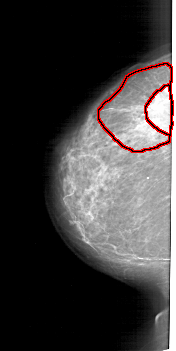

A_1827_1.LEFT_MLO

FILE: A_1827_1.LEFT_MLO.OVERLAY

TOTAL_ABNORMALITIES 1

ABNORMALITY 1

LESION_TYPE MASS SHAPE IRREGULAR MARGINS SPICULATED

ASSESSMENT 5

SUBTLETY 5

PATHOLOGY MALIGNANT

TOTAL_OUTLINES 2

BOUNDARY

CORE